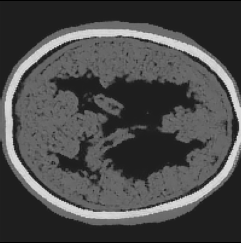

Refer to caption

(a) Partial-transducer dataset

Figure 8: Stacked TRA Image with (a) Partial-transducer dataset and (b) Full-transducer dataset

To evaluate performance, we construct two acquisition setups from the same horizontal 2D slice of the phantom: (i) an idealized full-transducer dataset (Figure 4(b)) providing near-uniform coverage along the head contour, and (ii) a partial-transducer dataset (Figure 7) designed to reflect practical acquisition constraints. In the partial setup, a linear array with 51-element is repositioned around the head; for each view, the central element transmits and all other 50 elements receive. The partial setup includes 50 sweeps covering the full 360, meaning that for each sweep, the source and receivers rotate by 360/50=7.2360/50=7.2^{\circ}. Sweeping 50 views yields, per 2D slice, a channel tensor of shape (T,Ns,Nr)=(5001,50,50)(T,N_{s},N_{r})=(5001,50,50). The key distinction between these two datasets is their aperture: full-transducer provides near 360 coverage in a single placement, whereas partial-transducer attains coverage by aggregating neastest 50 receivers in a single placement, which is only around 36. Particularly, the partial-transducer setup includes only 50 sweeps, while the full-transducer setup uses all receivers covering the entire brain, with each transducer acting as a source in turn while the others serve as receivers. Compared to the full-transducer, the partial-transducer achieves coverage by combining a much smaller number of views. For each sweep, we generate the forward wavefield g(𝐱,t|𝐠){{g}}(\mathbf{x},t|\mathbf{g}) and the back-propagated wavefield p~(𝐱,t|𝐠)\tilde{{p}}(\mathbf{x},t|\mathbf{g}) and generate the TRA fragment with Eq. (7) (example in Figure 7). With the physical TRA method, the TRA fragment can be stacked to give the stacked TRA image. To validate the differences between the two datasets, we generated stacked TRA images using both datasets, as shown in Figure 8. As shown in Figure 8(b), the full-transducer dataset provides significantly greater detail in internal structures. Despite higher levels of noise and artifacts caused by the limited number of views, the partial-transducer dataset is still capable of capturing some meaningful tissue structures.